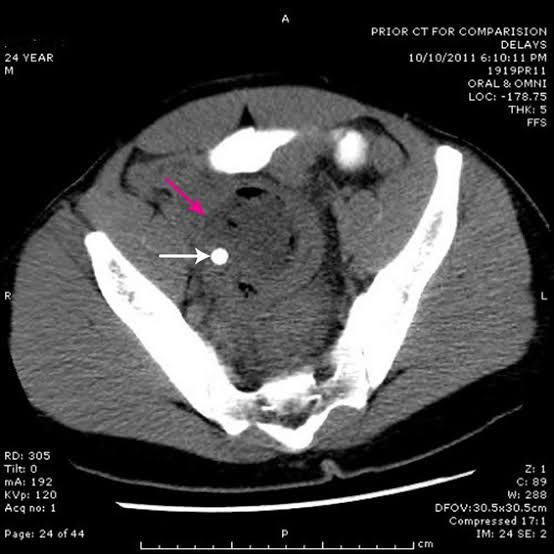

There can be one or more abscesses. CT scan of the pelvis showing a large intra-abdominal mass. ... You may have: Swollen belly. Diarrhea. Fever or chills. Lack of appetite and possible weight loss. Nausea or vomiting. Weakness. Cough.